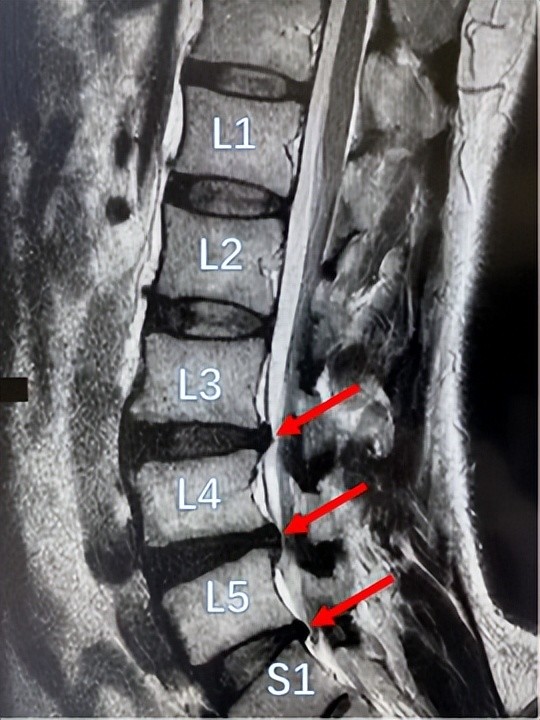

腰椎L1

腰椎L1,腰椎胸椎

腰椎l1到l5的图片

腰椎l1s1位置示意图

腰椎图形l1~l5排列

腰椎l3l4l5位置图片

腰椎l5一s1图解